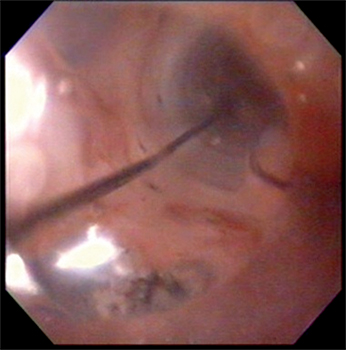

No se evidenciaron alteraciones patológicas significativas en el duodeno y en el estómago. Se realizó una dilatación esofágica en tres tiempos con balón neumático de expansión radial controlada (Boston Scientific ® 10-12 mm), hasta un máximo de 12 atmósferas, sin complicaciones inmediatas ni tardías posteriores al procedimiento (Figura 5).